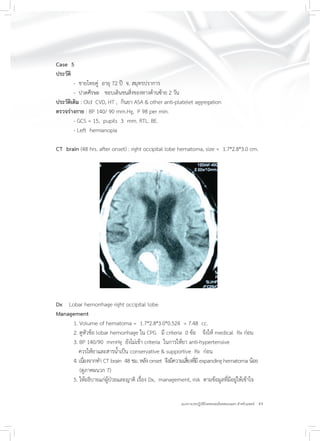

Case 5

ประวัติ

- ชายไทยคู่ อายุ 72 ปี จ. สมุทรปราการ

- ปวดศีรษะ ชอบเดินชนสิ่งของทางด้านซ้าย 2 วัน

ประวัติเดิม : Old CVD, HT , กินยา ASA & other anti-platelet aggregation

ตรวจร่างกาย : BP 140/ 90 mm.Hg, P 98 per min.

- GCS = 15, pupils 3 mm. RTL. BE.

- Left hemianopia

CT brain (48 hrs. after onset) : right occipital lobe hematoma, size = 1.7*2.8*3.0 cm.

Dx Lobar hemorrhage right occipital lobe

Management

1. Volume of hematoma = 1.7*2.8*3.0*0.524 = 7.48 cc.

2. ดูหัวข้อ lobar hemorrhage ใน CPG มี criteria 0 ข้อ จึงให้ medical Rx ก่อน

3. BP 140/90 mmHg ยังไม่เข้า criteria ในการให้ยา anti-hypertensive

ควรให้ยาและสารน้ำเป็น conservative & supportive Rx ก่อน

4. เนื่องจากทำ CT brain 48 ชม. หลัง onset จึงมีความเสี่ยงที่มี expanding hematoma น้อย

(ดูภาคผนวก 7)

5. ให้อธิบายแก่ผู้ป่วยและญาติ เรื่อง Dx, management, risk ตามข้อมูลที่มีอยู่ให้เข้าใจ